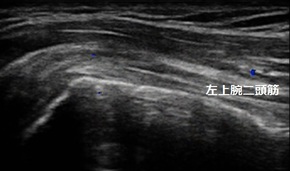

右肩患部 左正常側

右腕を前方や側方から肩の高さまで上げようとしても痛くて自力で腕の重みを支えられません。

超音波画像では患部のperibursal fatが落ち込んでいて断裂を示唆していました(画像⇩矢印)。また、筋肉の厚みも正常側と比較して減少していました(画像↕矢印)。

右腕を挙げようとすると首から肩などに痛みがひどく出るので疼痛改善する施術やマッサージを行います。日常生活では断裂の拡大を防ぐために力仕事や球技などのスポーツ、筋力トレーニングを休止します。